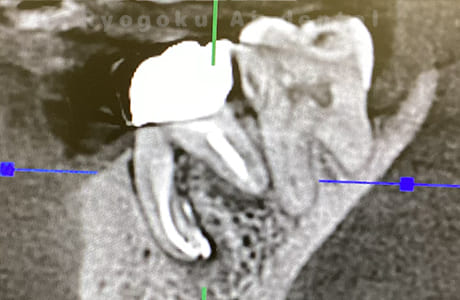

CTスキャンによる診断

すべての歯科治療において診査診断は非常に重要です。

CTスキャンによる検査をすることで歯根の状態をしっかり把握し治療計画を立てることができます。

診査診断をしっかりすることで治療の質の向上につながります。